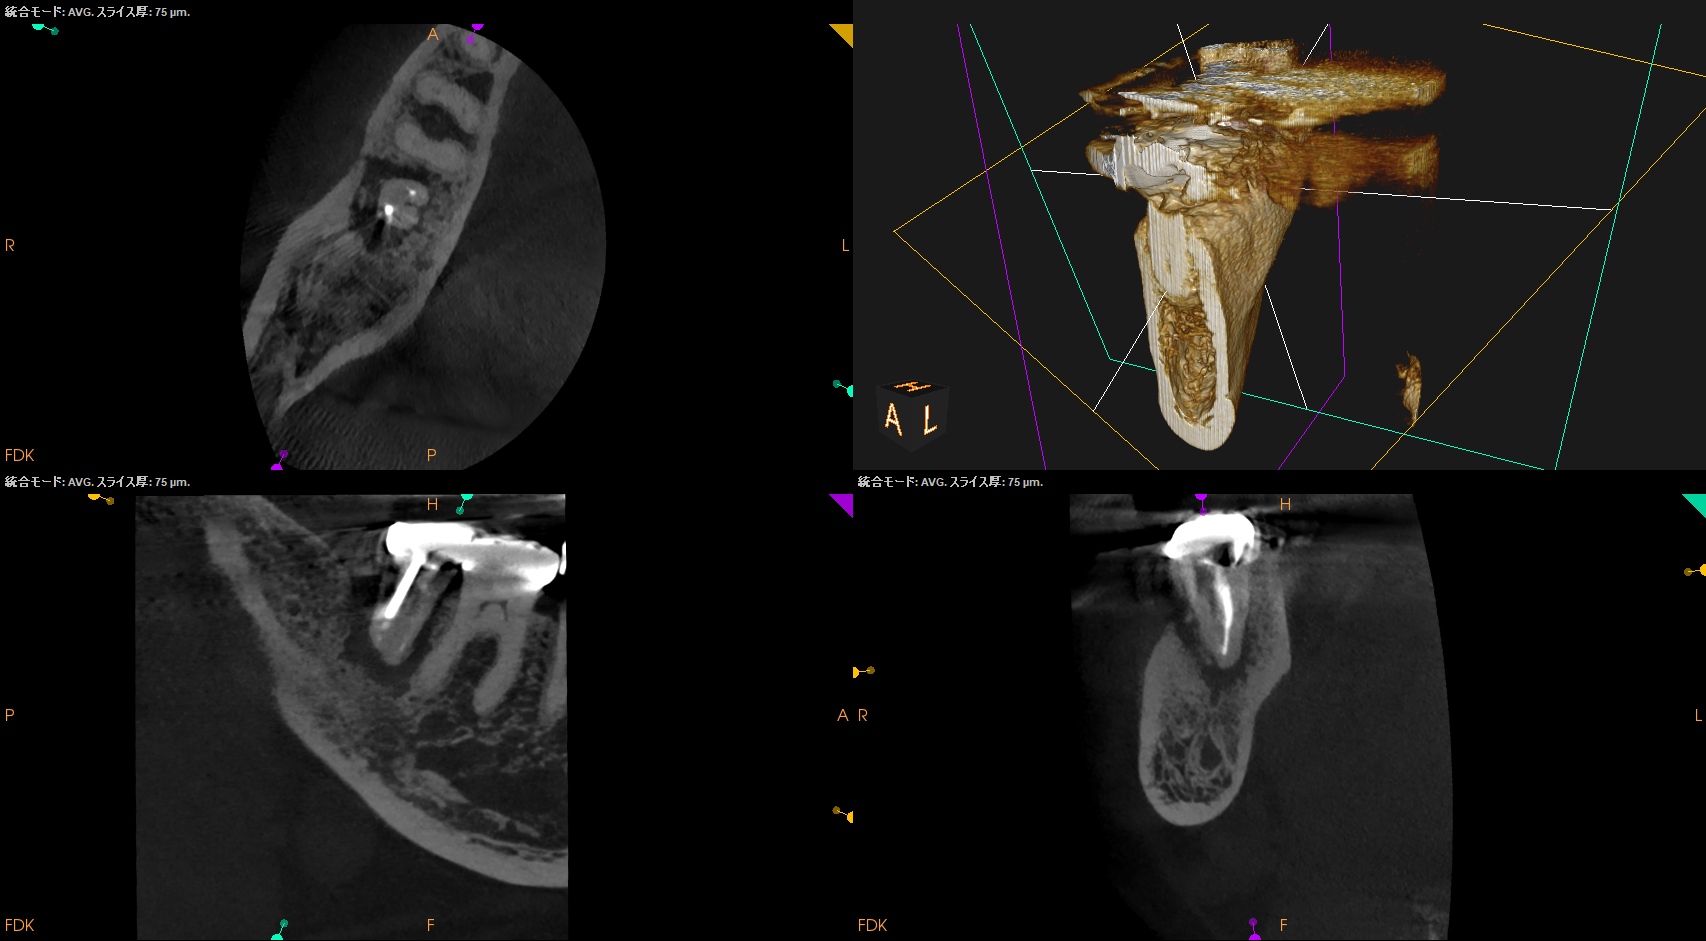

CBCT(2025.5.19)

ML

MB

D

確かに…

折れていると言われかねない状況だ。

が、何度も言うが

歯牙が折れているかどうか?は、その歯を抜歯して口腔外に出して直視しないとわからない

のである。

その意味でも、

Intentional Replantationこそがその真贋を見分ける治療方法であると言えるだろう。